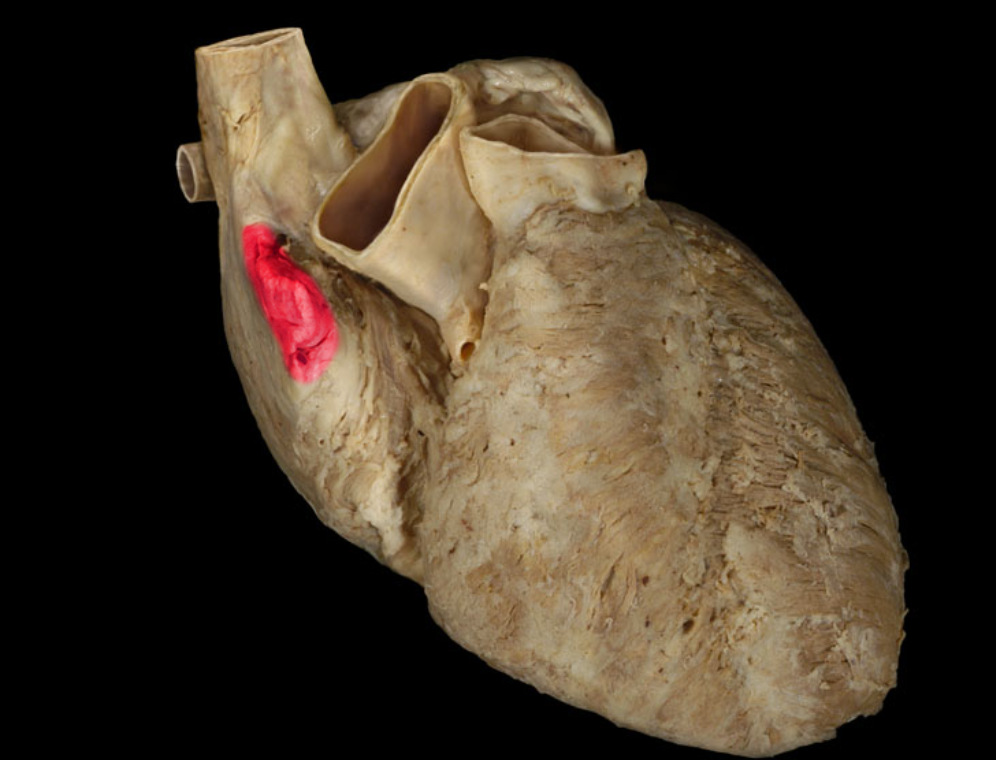

Right auricle

Right auricle